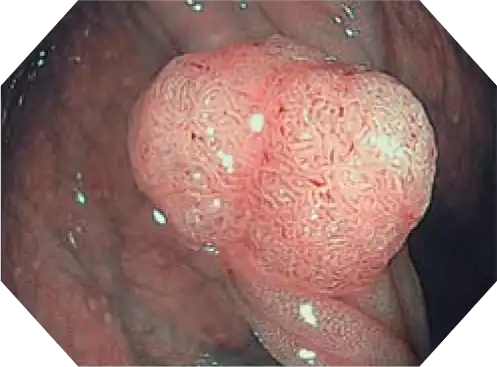

NBI (Narrow Band Imaging)

NBI in EVIS EXERA III 190 Series scopes provides twice the viewable distance of EVIS EXERAII 180 Series scopes and offers much greater contrast between blood vessels and mucosa. The greatly improved performance of NBI opens up exciting new clinical applications and reinforces NBI’s position as the standard of care for GI endoscopy.